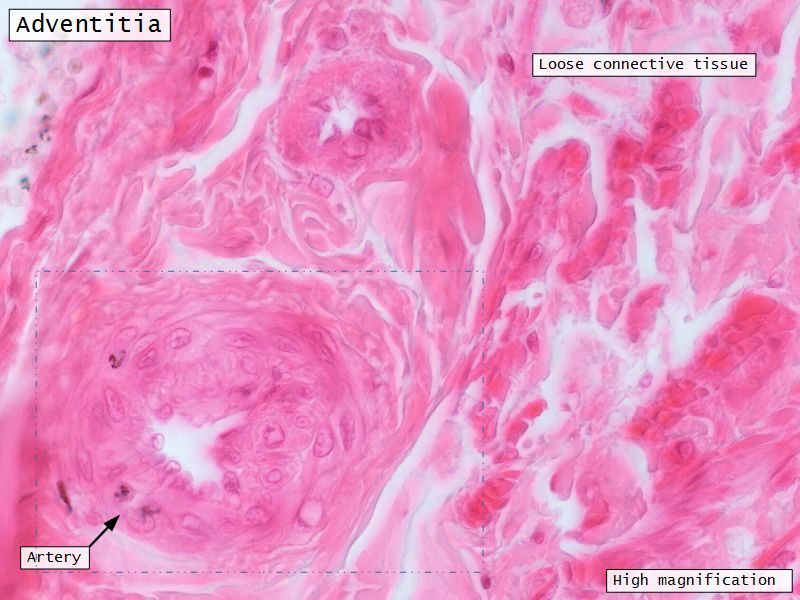

Adventitia

- Or serosa

- Covers myometrium

Adventitia

- Fibroelastic connective tissue

- Fixes onto surrounding structure

- Blood vessels and nerves

- Adventitia

- Loose CT with AVNL